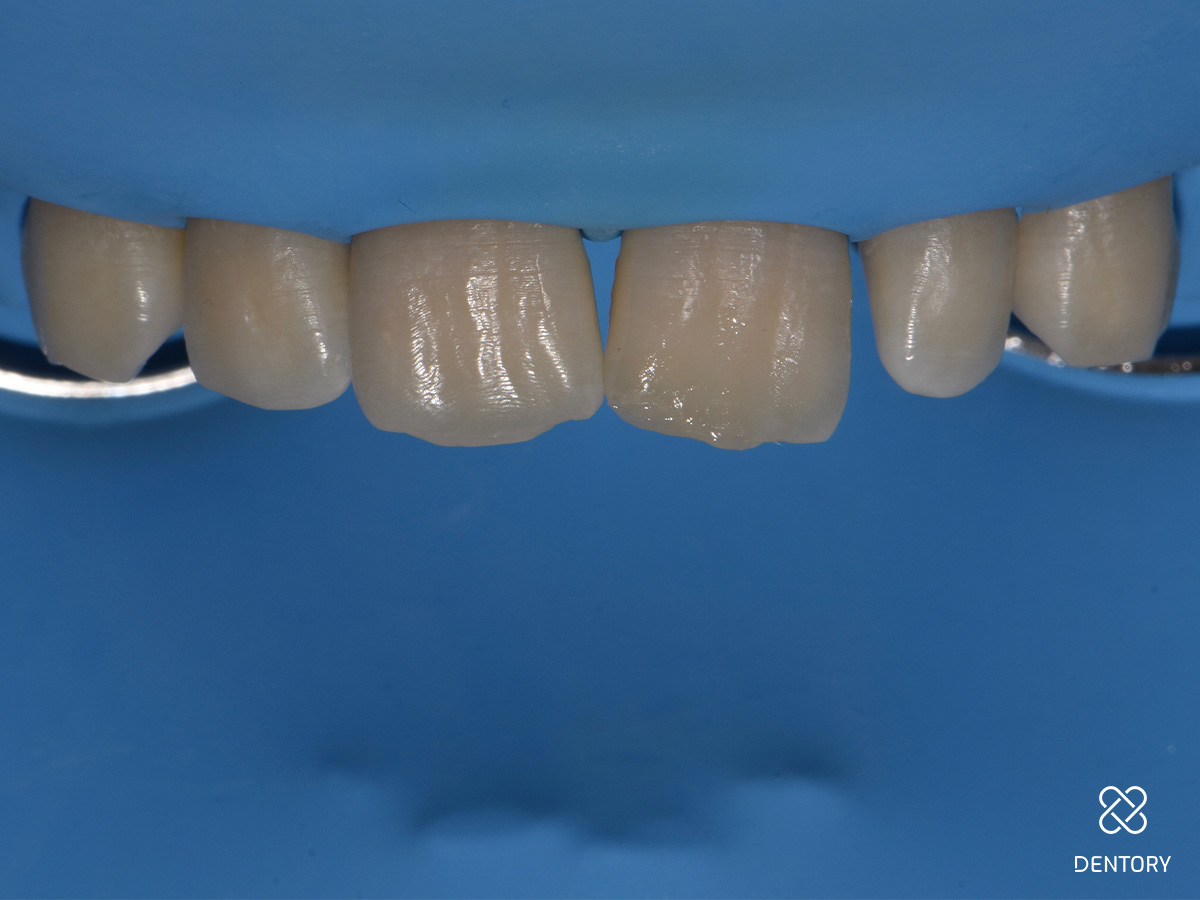

Abbildung 3

Eine breite, wellenförmig verlaufende Anschrägung sorgt für einen fließenden Übergang zwischen Zahn und Restauration hinsichtlich Form und Farbe. Scharfe Kanten und Ecken sollten abgerundet werden.